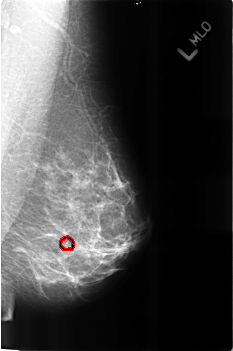

B_3160_1.LEFT_MLO

FILE: B_3160_1.LEFT_MLO.OVERLAY

TOTAL_ABNORMALITIES 1

ABNORMALITY 1

LESION_TYPE CALCIFICATION TYPE LUCENT_CENTERED DISTRIBUTION N/A

ASSESSMENT 2

SUBTLETY 4

PATHOLOGY BENIGN

TOTAL_OUTLINES 1

BOUNDARY

LEFT_MLO LINES 4560 PIXELS_PER_LINE 3024 BITS_PER_PIXEL 12 RESOLUTION 50 OVERLAY